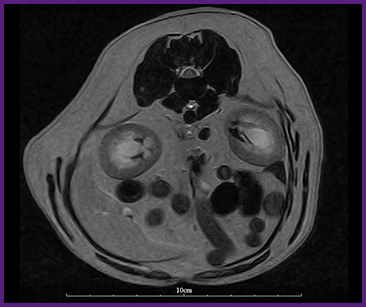

我們提供留院服務並擁有相應的治療設施,亦是小數備有CT電腦掃描及MRI磁力共振等大型醫療儀器的診所及醫院。